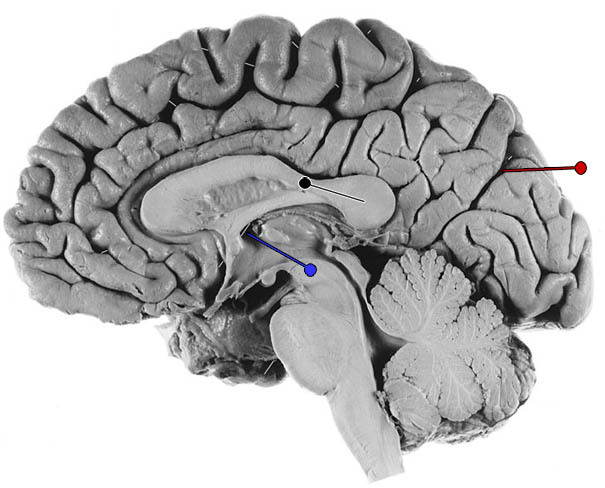

What is the channel indicated by the blue pin?

links one lateral ventricle to the third ventricle –> foramen of Monro.

Damage to which lobe of the brain would cause an interruption of flow through the inferior horn of the lateral ventircle?

temporal